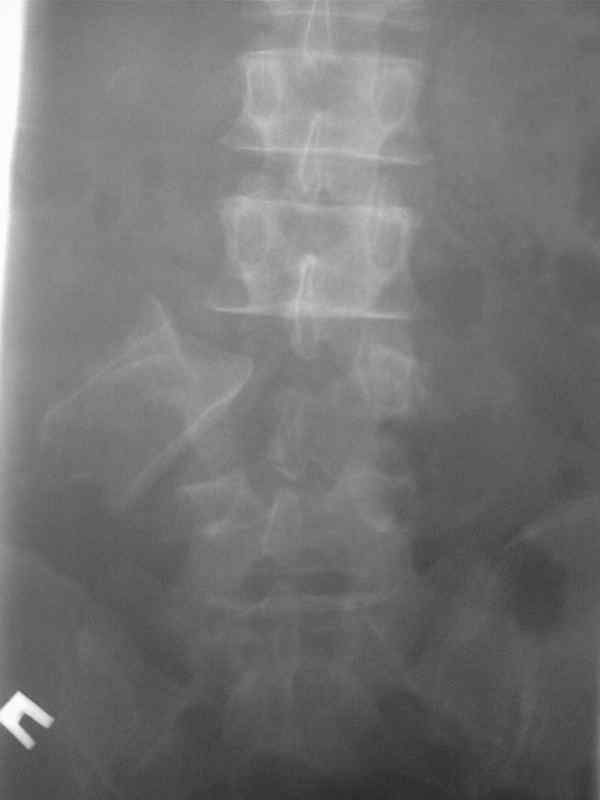

Сегодня видел вот такую травму позвоночника. Был весьма удивлен.